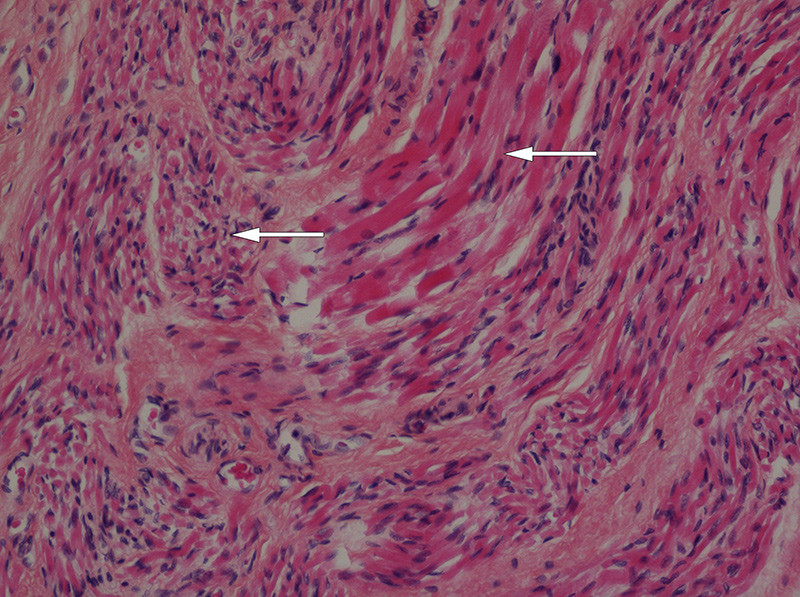

Ved obduksjon var det normale funn i hjerne, lillehjerne og hjernestamme. Diafragma var løvtynn, og i snitt fra diafragma og muskulatur i over- og underekstremiteter fantes en uttalt storgruppeatrofi. Primært ble det ikke beskrevet svinn av nerveceller i medulla spinalis.

2 1/2 år senere beskrev en annen nevropatolog nervecellesvinn i de motoriske forhorn i torakalmedulla, med fibersvinn i fremre røtter. Det var ikke fibersvinn i sensoriske røtter. Snitt fra perifere nerver viste fibrose og bare enkelte myeliniserte fibre. Det var ingen holdepunkter for Guillain-Barrés syndrom.

Ved obduksjon ble det funnet tynn diafragma, på kun 1 – 2 mm. Det var svinn av forhornceller i medulla spinalis (fig 1), med usedvanlig små fremre røtter (fig 2). Det var også mulig fibersvinn i kortikospinale baner gjennom hele hjernestammen og i tractus corticospinalis lateralt i medulla. I diafragma fantes spredte grupper av atrofiske fibre og spredte hypertrofiske fibre (fig 3). I skjelettmuskulatur fantes områder med muskelatrofi (fig 4). Det ble fortsatt konkludert med en variant av Werdnig-Hoffmanns sykdom.

De nevropatologiske funn hos disse pasientene varierer. Hos alle finner man muskelatrofi, og mange beskriver forandringer i perifere nerver. Selv om tilstanden oppfattes som spinal muskelatrofi, har ikke alle funnet de forandringer i medullas forhornceller som man ville vente (7). Hos våre pasienter som ble undersøkt, beskrives svinn av nevroner. Både nevropatologiske funn og nevrofysiologiske resultater tyder på perifer aksonal affeksjon og/eller progredierende affeksjon av både motoriske og sensoriske nevroner, der motoriske nevroner blir tidligst og mest affisert.